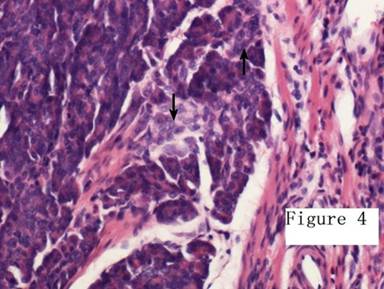

An emergency laparotomy was performed immediately. Intraoperative colonoscopy did not identify the source of bleeding. A Meckel’s diverticulum was found about 60 cm proximal to the ileocecal valve on the antimesentery side. Consequently diverticulectomy was carried out. Gross examination of the specimen revealed a 1.0 cm diameter mass supplied by varicose vessels arising from the distal end of the diverticulum (Figures 1 and 2). There was an ulcer on the mucosal surface of the diverticulum. On dissection the cut surface was yellowish. Histological examination revealed the presence of pancreatic acini, ducts and islets of Langerhans (Figures 3 and 4). The patient was discharged uneventfully. At his 8-month follow-up, there was no evidence of recurrence.

Figure 4. Histological section (H&E x200) showed the pancreatic acini (up arrow) and islet of Langerhans (down arrow). |